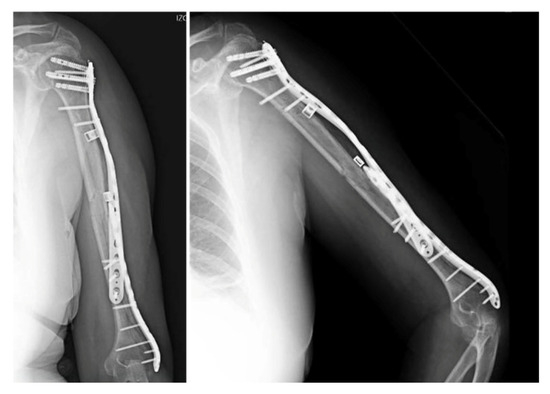

After removing the intramedullary implant, a rotator cuff repair was carried out at the nail’s insertion site in order to allow a speedy functional recovery. Subsequently, an extended posterior approach to the elbow was performed, proximally prolonged to the medial side, following a spiral-shaped trajectory. During the procedure, the radial and ulnar nerves were identified and dissected (Figure 3).

After reducing the fragments under fluoroscopic guidance, the two plates used to fix the fractures were supplemented by a locked extraarticular plate (LOQTEQ, aap Implantate AG, Berlin, Germany). Subsequently, and after a preliminary stabilization with K-wires, the fixation was reinforced by means of a long locked proximal humeral plate (Pantera, Toby Orthopaedics, Miami, FL, USA), which was helically contoured. The intermediate fragments were controlled using polymer cerclage bands (Ortholox, Ortolog Medical, Ankara, Turkey). Before closure, the stability of the fixation and the patient’s dynamic range of motion were checked and antibiotic-loaded calcium sulfate beads (Stimulan, Biocomposites, Staffordshire, UK) were applied as prophylaxis, as a local adjunct to systemic antibiotic therapy to enhance infection control in the context of a prolonged reoperation (Figure 4). Given the acute nature of the fracture, neither bone grafting nor postoperative electromagnetic therapy was deemed necessary. Initial immobilization was achieved by means of a Robert Jones bandage. Postoperative recovery proceeded uneventfully, with physical therapy being progressively introduced.

Figure 4. Postoperative anteroposterior view. Osteosynthesis with two precontoured helical plates and Stimulan antibiotic beads.